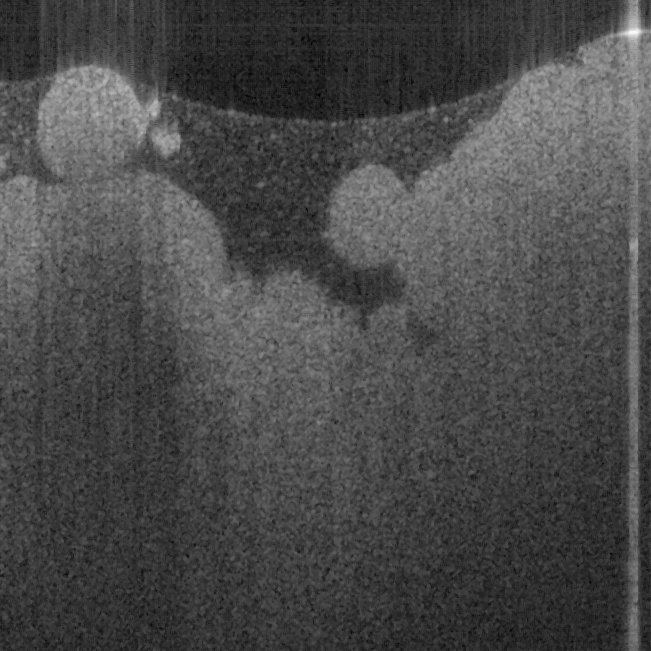

Fig. 16. In vivo human finger SS-OCT images taken with probe #14 (working distance, depth

of field and spot diameter of 1.2 mm 1.1 mm, and 27 m) and # 16 (working distance, depth

of field and spot diameter of 0.9 mm 0.33 mm, and 16 m) acquired by our catheter-based

complex SS-OCT using our 3x3 Mach-Zehnder interferometer with unbalanced differential

detection technique with image size of 5x2mm.

The image depth shown in Fig. 16 (a) is slightly larger than that in Fig. 16 (b), but the image

is blurrier in Fig. 16 (a) than that in Fig. 16 (b), which taken by the probe with larger depth of

field and spot size. The image shown in Fig. 16 (b) has higher resolution than that in Fig. 16

(a), which can be seen clearly with finer structures in layer of epidermis (grey arrow), sweat

gland (white arrow), and blood vessel in subcutis layer (black arrow).